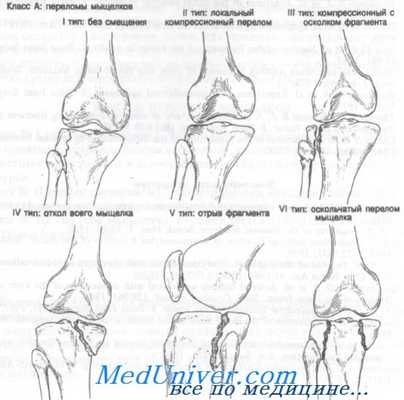

Класс А: переломы мыщелков

Класс А: переломы мыщелков большеберцовой кости

Переломы мыщелков большеберцовой кости встречаются нередко. Они были классифицированы Hohl на основании анатомических данных и принципов лечения. Рассматривая переломы мыщелков большеберцовой кости, следует указать, что под отломом мыщелка имеют в виду смещение вниз его более чем на 4 мм. Серьезная деформация коленного сустава может возникнуть после, казалось бы, незначительных переломов проксимального отдела большеберцовой кости у детей. Причина ее остается неясной. Она появляется у детей до 4-летнего возраста и проявляется вальгусной деформацией коленного сустава через 6—15 мес после травмы.